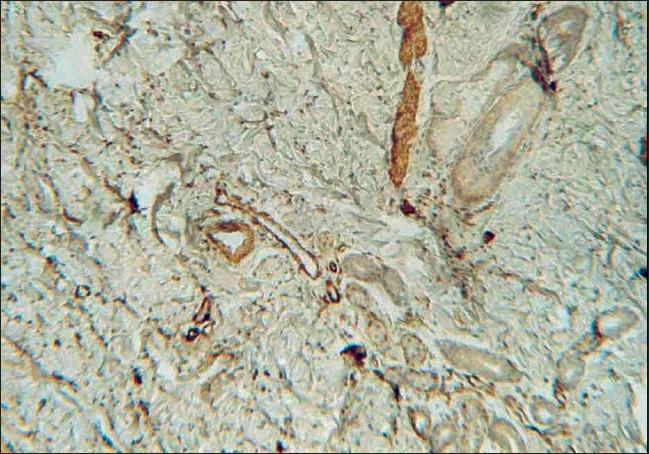

Smooth muscle hamartoma (SMH) is a proliferative disorder of cells originating from muscle cells. It is a benign tumoral mass that usually presents as a single congenital skin-colored and hypertrichotic plaque involving the trunk and extremities. Multiple SMHs have rarely been reported in the literature. We describe the case of a seven-month-old girl with multiple SMHs located over the back and arm areas. The diagnosis was confirmed by biopsy and immunohistochemical (IHC) staining. She had no cerebral or skeletal abnormalities and her growth and development were normal.

平滑肌瘤(SMH)是一种起源于肌细胞的细胞增殖性疾病。它是一种良性肿瘤性肿块,通常表现为单个先天性肤色且多毛的斑块,累及躯干和四肢。文献中很少报道多发性SMH。我们描述了一名7个月大女童的病例,其背部和手臂区域有多发性SMH。通过活检和免疫组织化学(IHC)染色确诊。她没有脑或骨骼异常,生长发育正常。